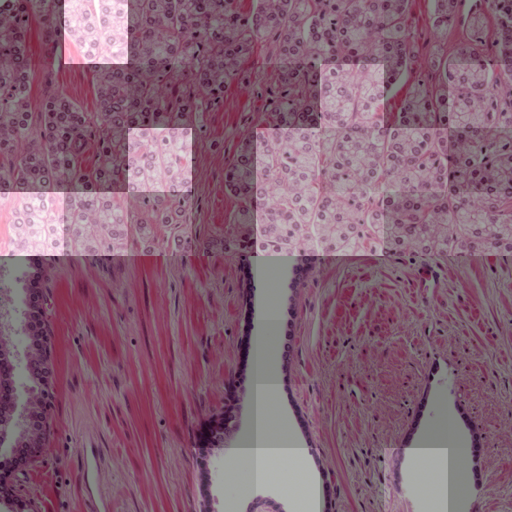

Another experiment was conducted on the survival dataset. From each TMA, one image was randomly chosen from both the validation and test sets of the survival dataset, while maintaining the overall data distribution with respect to the ISUP grades, relapse time and censoring status. An expert pathologist marked tumor regions in each image, enabling us to compare this to the attention weights per patch. A patch is counted as tumorous if 66% of it lie within the marked tumor region. \figurereffig:annotation_example_img shows that all highlighted patches lie within the tumor area, however not all patches in the tumor area receive a high attention weight. \figurereffig:annotation_example_box shows the results on all images showing tumor tissue drawn from the test set. Patches marked as tumor show on average higher attention weights than non-tumor image patches.